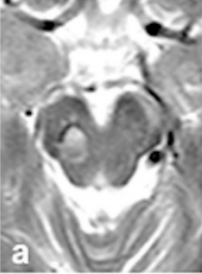

圖a:術(shù)前6個(gè)月MRI顯示輕度出血

圖b和c:顯示22mm出血性中腦海綿狀血管瘤,向尾側(cè)延伸